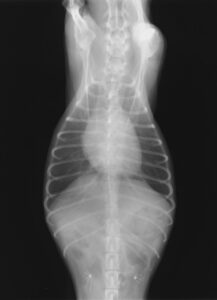

レントゲン検査

レントゲン検査では

- 心臓の大きさ

- 肺の状態

- 血管・気管・気管支の状態

の評価を行います。

後述するACVIMのステージ分類の際にもレントゲン検査による心臓のサイズの確認は重要となります。

肺水腫あり

治療後

レントゲン検査は数分で実施可能です。最低2方向以上撮影を行い評価します。

呼吸の状態が悪い子などは酸素をかがせながら行ったり、うつ伏せのみの撮影にしたりする場合もあります。